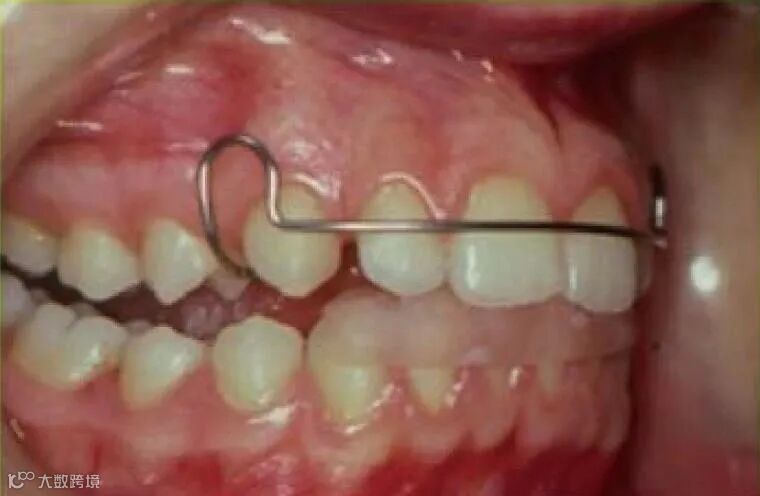

使下颌处于前伸位置,使相关的肌肉做出反应,从而获得纠正牙齿、牙弓关系所需的正畸力,而最终目标是改善患者面貌,见图1~图2。

图1 肌激动器口内侧面像